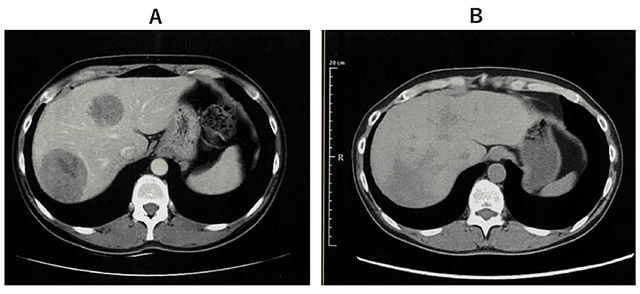

2024年3月28日,医学期刊《Cureus》报道了一例晚期宫颈癌患者通过WT1-DC疫苗+纳武利尤单抗等联合疗法成功实现肿瘤完全消退的突破性病例。

患者为50多岁女性,既往接受了手术、放化疗,但很快便出现淋巴结转移(右锁骨上窝、气管旁)及肝转移。更改方案1个月后肝转移灶仍旧快速进展。

由于肝脏60%体积已被两个巨大转移灶占据,接受全肝放疗后,转移灶显著缩小。随后,医生尝试创新性免疫联合疗法:肾母细胞瘤 1 脉冲树突状细胞疫苗疗法(WT1-DC)+纳武利尤单抗。幸运的是,第5次WT1-DC注射后,CT显示肝转移灶完全消失。治疗期间出现高热(≥39°C),但可自行缓解。